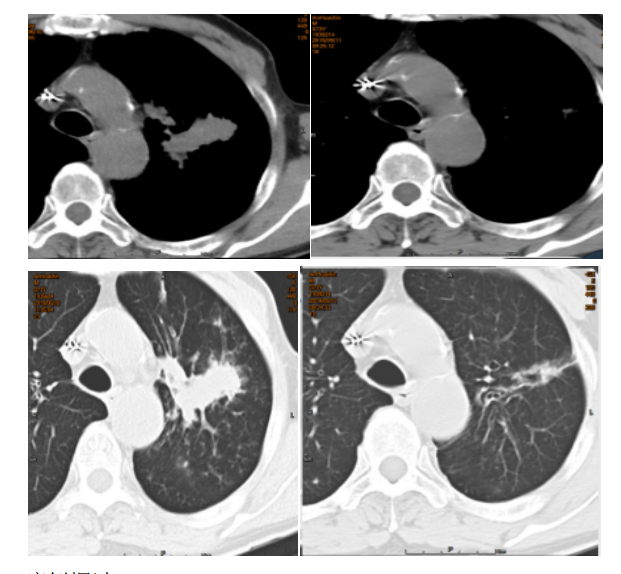

9月化疗后复查胸部CT:与2019-06-10比较,左肺上叶高密度影,明显缩小;双肺多发小结节,无著变。原双肺散在点状模糊阴影明显吸收。

6月10日(左)及9月11日(右))胸部CT对比

(1)化疗方案:本患者采用GP方案3周期化疗,其中吉西他滨是一种具有独特作用机制和不良反应特点的新型抗嘧啶核苷酸代谢的化疗药物,它可以增加铂类化疗药物与 DNA 嵌合的稳定性并抑制损伤后的修复,故与铂类化疗药物之间有协同作用。患者采用GP方案治疗后,患者未见恶心呕吐等明显不适症状,并且化疗后复查胸部CT示肿块较前明显缩小,考虑GP方案疗效显著。